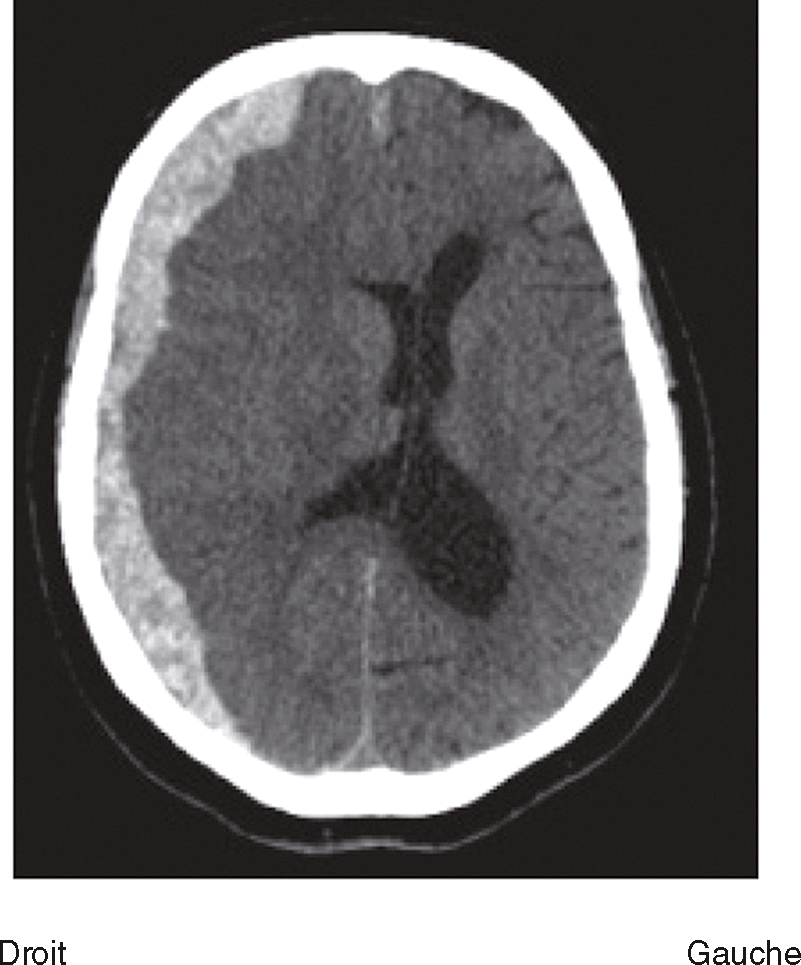

Une nouvelle IRM cérébrale est réalisée devant cette diplopie. Décrivez le cliché (fig. 31.1).

L'image montre une coupe transversale d'un cerveau humain obtenue par imagerie par résonance magnétique (IRM). Cette image est une vue axiale, ce qui signifie qu'elle est prise horizontalement à travers le cerveau. On peut observer les différentes structures cérébrales, y compris la matière grise et la matière blanche. Les ventricules latéraux, qui sont des cavités remplies de liquide céphalo-rachidien, sont visibles au centre de l'image. Les zones plus claires autour des ventricules peuvent indiquer des anomalies ou des lésions, souvent associées à des conditions neurologiques comme la sclérose en plaques. Les contours du cerveau sont bien définis, et les différentes régions du cortex cérébral sont clairement visibles. Cette image est intéressante car elle permet aux médecins de diagnostiquer et de surveiller diverses maladies neurologiques en visualisant les structures internes du cerveau avec une grande précision. L'IRM est une technique non invasive qui utilise des champs magnétiques et des ondes radio pour produire des images détaillées des organes et des tissus internes, ce qui est crucial pour la détection précoce et le traitement des maladies cérébrales.

- C hypersignaux de la substance blanche périventricu-laire

- D hypersignaux du tronc cérébral

- E hypersignaux juxtacorticaux